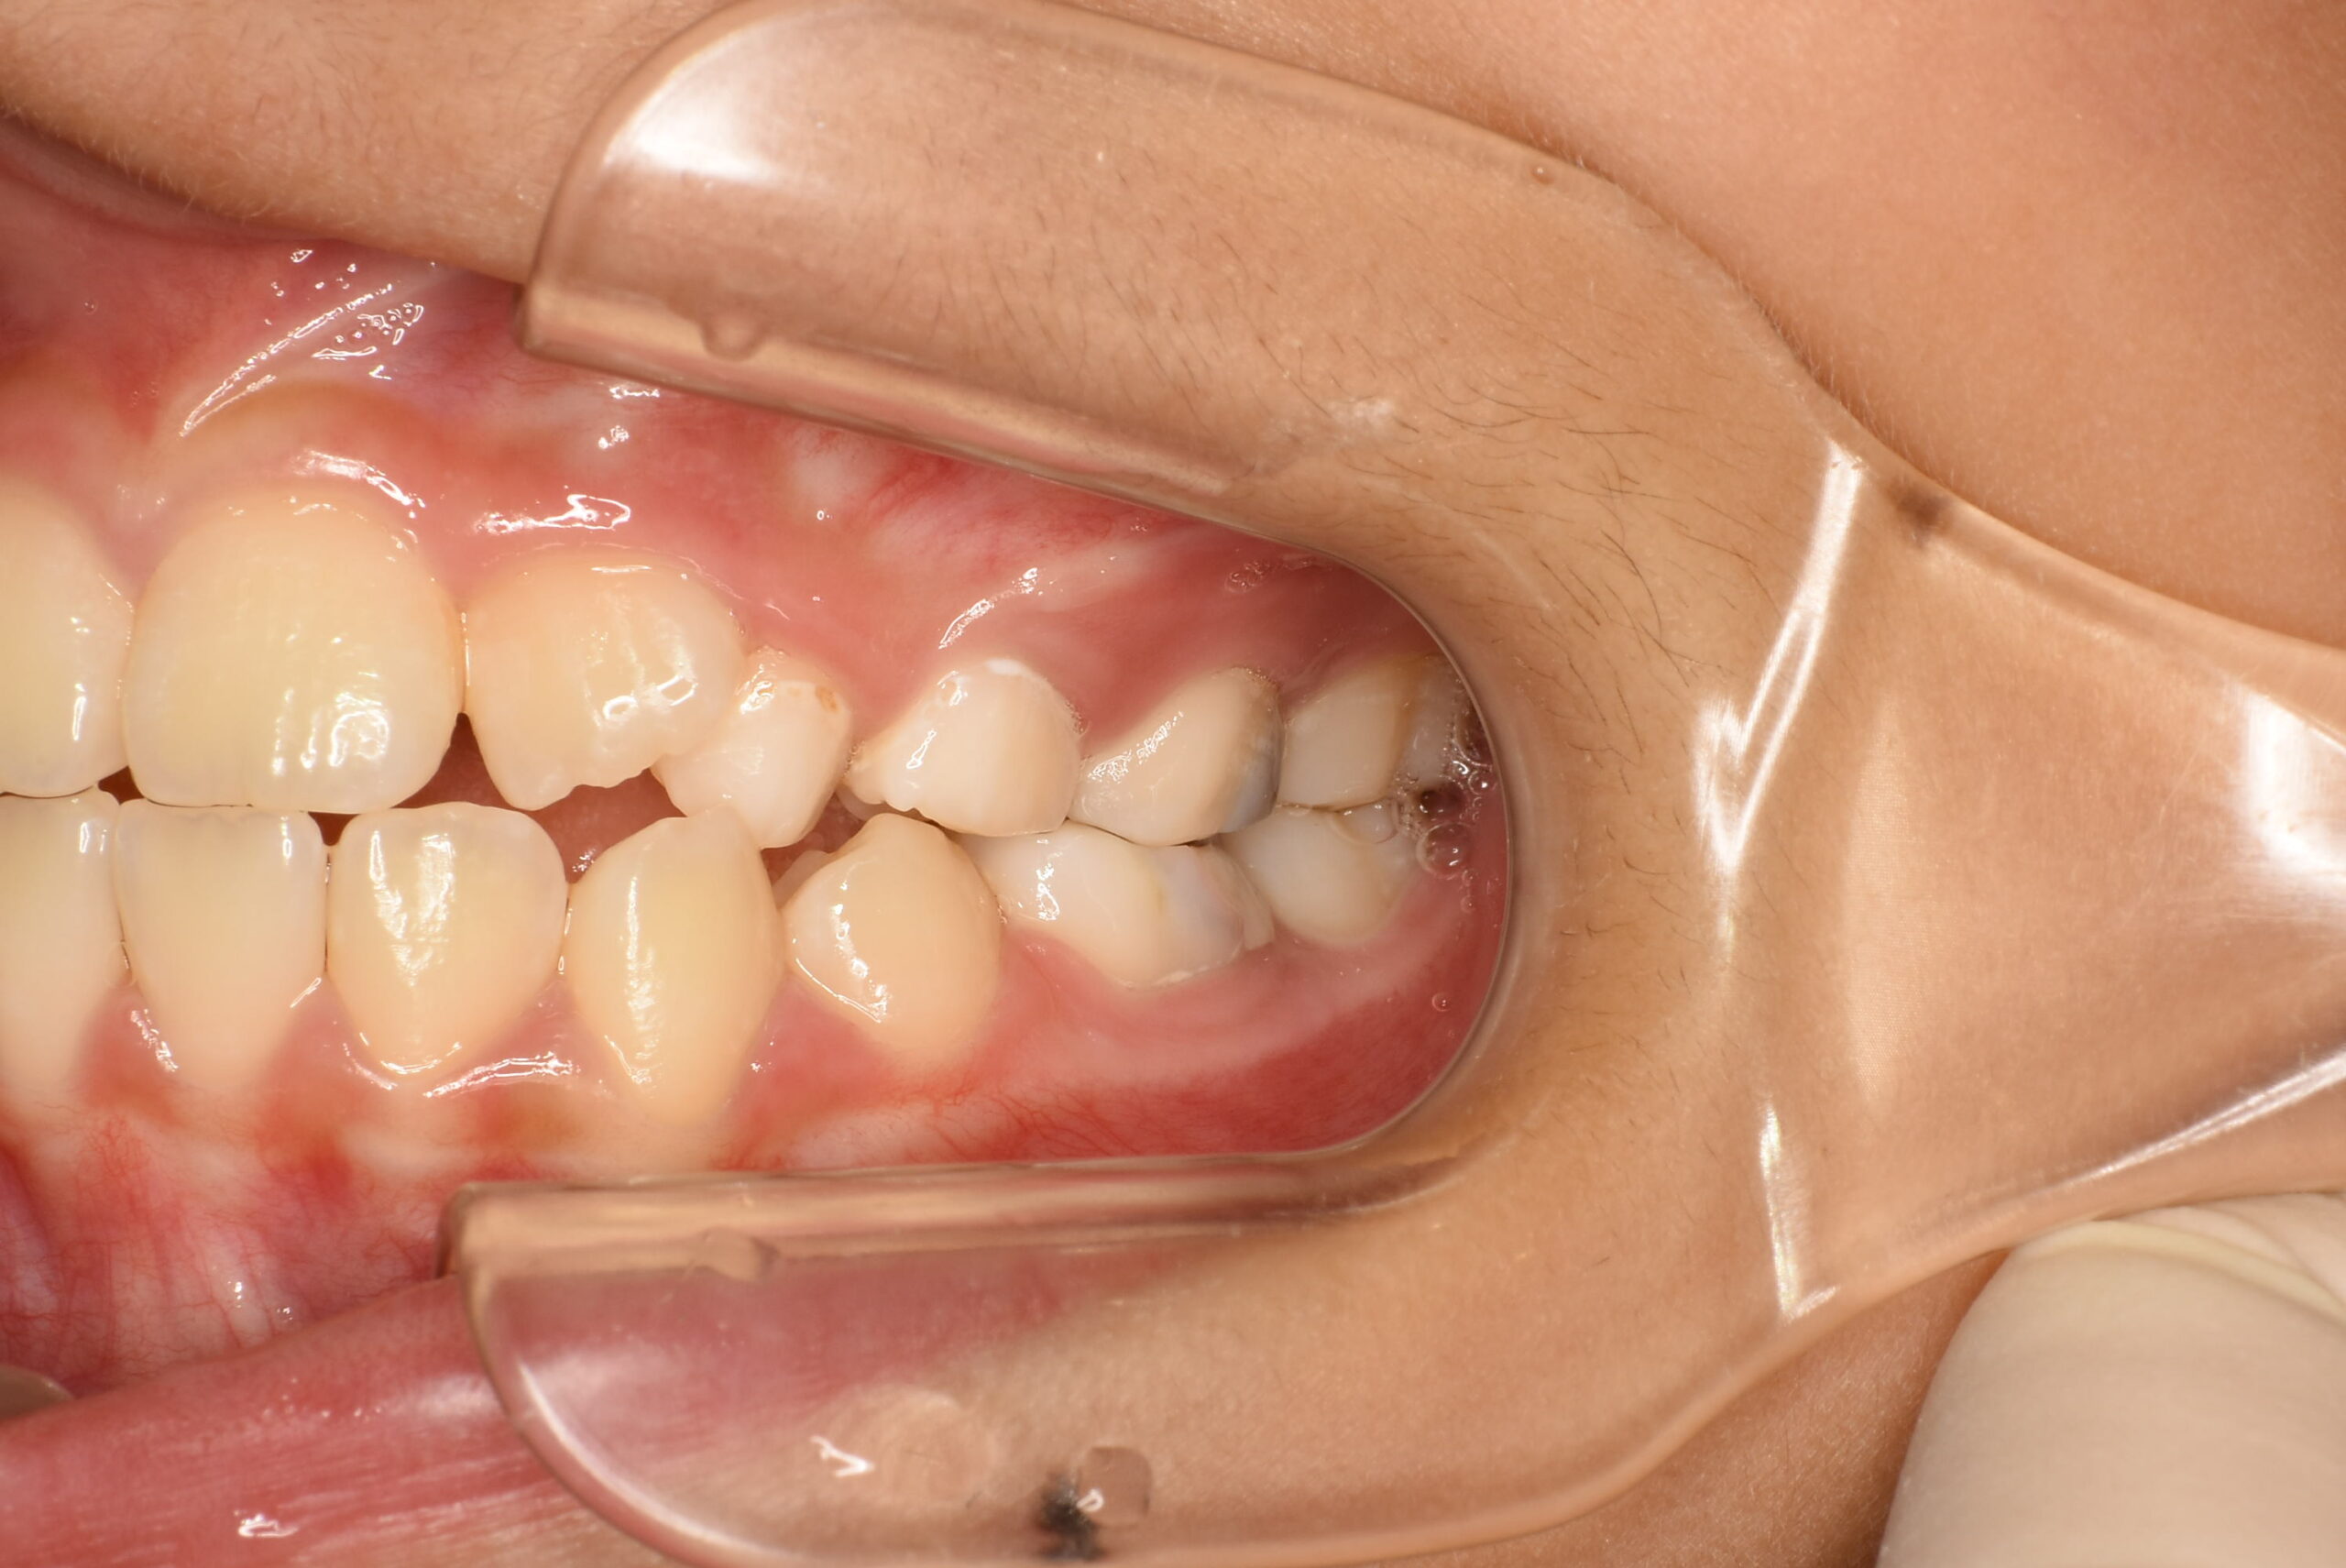

症例詳細:マイオブレースを用いた小児矯正(咬合誘導)

| 主訴 | 出っ歯 |

|---|---|

| 年齢・性別 | 女児・10歳(小学4年生) |

| 診断名 | 上顎前突(出っ歯)、口呼吸および舌の癖 |

| 治療内容 | 日中1時間と就寝時のマウスピース装着に加え、呼吸・舌・飲み込み・唇を鍛えるトレーニング(アクティビティ)を毎日実施。 |

| 治療期間 | 2年2か月(現在も継続中) |

| 費用(税込) | 583,000円 ※検査代・装置代・月1回調整料5,500円含む |

| リスク・副作用 |

|

| 備考 | 本症例は治療途中の経過写真です。治療結果には個人差があります。 |